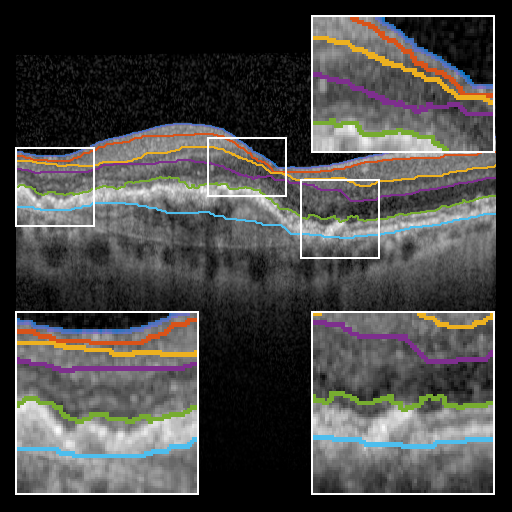

Optical Coherence Tomography (OCT) is a non-invasive medical imaging modality that provides micrometer-resolution volumetric scans of biological tissue [8]. Since its introduction in 1991, OCT has seen widespread use in the field of ophthalmology, as it enables direct, non-invasive imaging of the retinal layers. As shown in Fig. 1OCT allows for the visualization of both healthy tissue and pathological biomarkers such as drusen, cysts and fluid pockets within and underneath the retinal layers. Critically, these have been linked to diseases such as Age-related Macular Degeneration (AMD), Diabetic Retinopathy (DR) and Central Serous Chorioretinopathy (CSC[1, 13].

Figure 1: Example of OCT cross-sections with retinal layer boundaries highlighted for (left) healthy subject and (right) late-stage AMD patient. The images were manually annotated by an expert ophthalmologist.